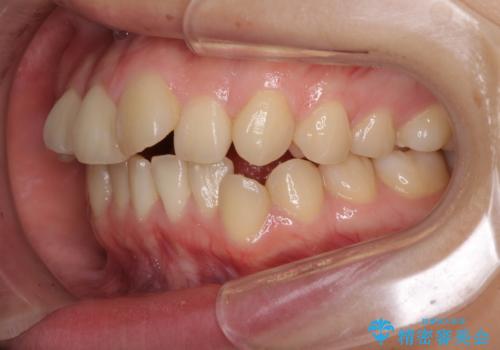

- デコボコと飛び出した前歯を治したいとのことで来院された患者様です。

ゴムかけを活用して上顎歯列全体を後方移動し、IPR(歯と歯の間を削る)によってデコボコが解消するように設計し、インビザラインにより治療を行うこととしました。

後方移動に際し、上下顎の親知らずは4本とも抜歯することとしました。

毎日しっかりと装着してくださったので、概ねシミュレーション通りに歯を移動させることができました。

治療前には接触することのなかった上下の前歯が接触するようになり、食事の際前歯でものをかみ切れるようになりました。

気にしていた口元の印象が改善され、患者様には大変満足していただきました。